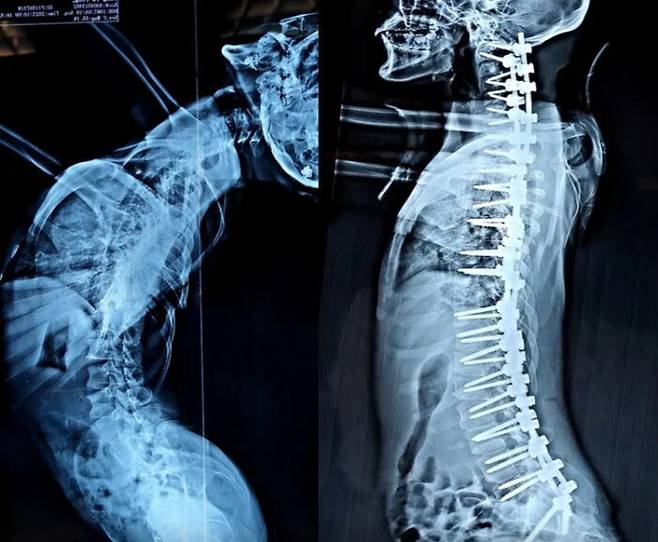

하지만 척추를 바로잡는 수술을 받은 후 공개된 영상에서는 그가 똑바로 서 있는 모습을 볼 수 있다. 휘어진 허리 때문에 수술 전 선 키가 120cm 정도 밖에 되지 않았던 그녀는 이제 160cm가 됐다. 수술은 베이징대학병원 정형외과의 왕유 박사가 집도한 것으로 알려졌다.

![수술 전후 엑스레이 사진 [사진='더선' 보도내용 캡처]](https://img1.daumcdn.net/thumb/R658x0.q70/?fname=https://t1.daumcdn.net/news/202312/11/KorMedi/20231211110514900qkqh.jpg)